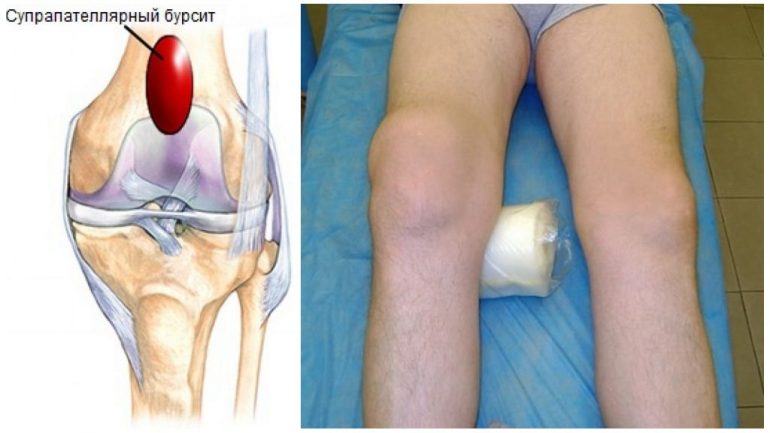

Супрапателярний бурсит коліна розвивається через запалення навколосуглобової сумки. Хвороба може спричинити серйозні ускладнення, зниження працездатності та інвалідизацію. Рання діагностика й адекватне лікування дозволяють подолати цю загрозу.

Навколосуглобові сумки — бурсі — це мішечки, наповнені синовіальною рідиною. Вони розташовані між м’язами, зв’язками, сухожиллями, кістками та шкірою. Виконують захисну, трофічну й амортизуючу функції, зменшуючи тертя між різними тканинами. Колінний суглоб оточений одинадцятьма таких сумок, кожна з яких має своє призначення. Залежно від локалізації ураженої бурси розрізняють такі види бурситу:

| Супрапателярний | Патологічні зміни надколінної сумки, що розташована над колінною чашечкою між квадрицепсом і великою гомілковою кісткою. Ця бурса є найбільшою й безпосередньо сполучається з порожниною колінного суглоба. |

За певних умов у навколосуглобових сумках розвивається запальний процес. Це проявляється зміною складу та в’язкості синовіальної рідини, накопиченням ексудату, інколи з мікроорганізмами або кров’ю. Супрапателярний і інфрапателярний бурсити коліна можуть протікати або з різким швидким початком, або поступово, з переходом у хронічну форму.

Прояви супрапателярного бурситу колінного суглоба залежать від стадії хвороби та ступеня її занедбаності.

| Гострий бурсит | Різкий пульсуючий біль у нападах. У ділянці коліна з’являється болюча припухлість, що швидко наростає. Інтенсивний болючий синдром обмежує рухи суглоба, ускладнює ходьбу й фізичну активність. Виникають набряк, почервоніння та локальне підвищення температури м’яких тканин навколо коліна. Можлива часткова або повна втрата функції згинання та розгинання коліна. Підвищення загальної температури, озноб, нічні потовиділення. Загальна слабкість і нездужання. |

| Хронічний бурсит | Тривала наявність припухлості й набряклості в області коліна. Почервоніння зменшується, локальна температура нормалізується. Частково або повністю відновлюється рухливість суглоба. Загальне самопочуття покращується, виникає відчуття полегшення. |